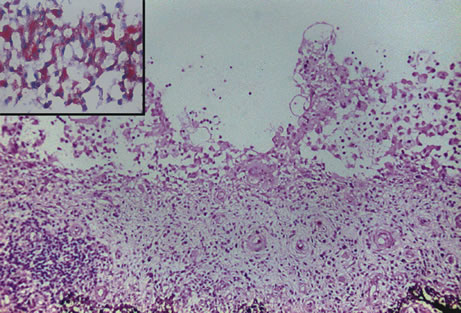

Infectious endophthalmitis refers to inflammation due to an infectious organism, usually bacterial, but it may also be caused by yeast or filamentous fungi. The vitreous is typically involved and supports the growth of the infectious intraocular organism. The reaction to the organism is usually severe and is characterized by abundant polymorphonuclear leukocyte infiltration. The infection is usually accompanied by tissue destruction due to the release of proteolytic enzymes in the severe inflammatory reaction. Uveal and retinal necrosis may occur during these infections. Endogenous endophthalmitis refers to hematogenous dissemination of organisms to the eye and can be seen in cases of septicemia from bacterial or fungal causes. The latter can be caused by Candida or Aspergillus species. Aspergillosis usually causes destructive choroidal inflammation (Fig. 24) with vascular occlusions. The infective organisms are found in the choriocapillaris or along the sub-RPE and sub-retinal space.126

Fig. 24. Aspergillus chorioretinitis. A. Hemorrhagic necrotizing retinitis and choroiditis are noted in a patient with disseminated aspergillosis (hemotoxylin-eosin ×60). B. Note the branching hypae of the organisms involving the retina and choroid (periodic acid–Schiff ×240).